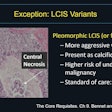

Dr. Susan Harvey, director of breast imaging at Johns Hopkins.

Dr. Susan Harvey, director of breast imaging at Johns Hopkins."Mortality from breast cancer has decreased significantly since 1990, probably related to improved mammography technology and detection, increased public awareness of the value of screening, and more effective treatments," the authors wrote. "Despite these improvements, breast cancer remains a serious health concern and is the second leading cause of cancer death among all women."